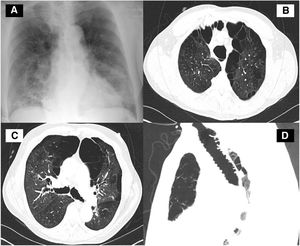

A 65-year-old man with a past medical history of recurrent pneumonia up to 8 times in the past 5 years presented to our institution with the chief complaint of a productive cough and shortness of breath over the preceding 2 weeks. Physical examination was remarkable with crackle heard on auscultation of both lungs. Complete blood count was remarkable for leukocytosis. The comprehensive metabolic panel was unremarkable. Chest radiography (Fig. 1A), demonstrated peripheral opacities in the mid and lower lung zones bilaterally. Computerized tomography (CT) of the chest revealed dilation of the trachea (Fig. 1B and D) and bronchiomegaly (Fig. 1C) with severe bullous paraseptal emphysema. Groundglass opacification and nodular consolidation right middle lobe. The clinical history of recurrent chest infections and a combination of imaging findings were consistent with Mounier-Kuhn Syndrome (MKS). The patient was treated with antibiotic and educated to improve airway clearance techniques.

(A) Chest radiograph revealed peripheral opacities in the mid and lower lung zones bilaterally. (B) Thoracic CT at a level above the aortic arch shows tracheomegaly severe bullous paraseptal emphysema. Groundglass opacification and nodular consolidation right middle lobe. (C) Thoracic CT at a level slightly below Carina demonstrated dilated right and left main bronchi with severe bullous paraseptal emphysema. Groundglass opacification and nodular consolidation right middle lobe. (D) CT image of the trachea (sagittal view) showing tracheomegaly.